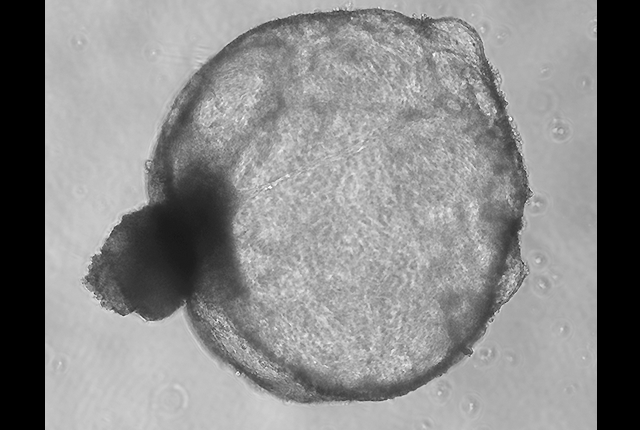

Microscopic image of a kidney cyst indicative of polycystic kidney disease, grown in a human organoid model. credit: Ramila Gulieva/Freedman Lab

“It's a novel idea to have tiny organoids that respond in the same exact way that a kidney would. You see (polycystic kidney) disease materialize before your eyes. The cyst structures that are characteristic of the disorder, you can see in three dimensions,” he said.

Polycystic kidney disease, commonly called PKD, affects 12.5 million people worldwide and is one of the most common inherited genetic disorders. The disease is characterized by fluid-filled sacs that develop in the kidneys and curb the organs' function. Patients typically show symptoms in their 30s, progress rapidly and need kidney transplants by their 50s. Aside from the faltering kidneys, other organ systems decline in parallel.